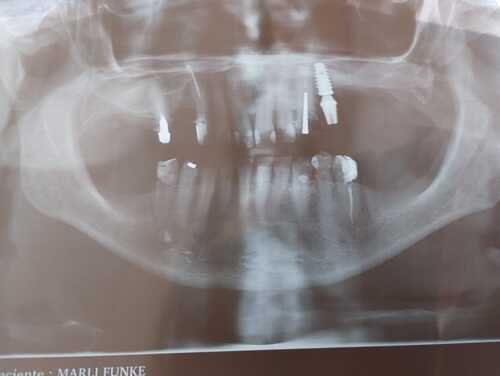

Estou na fase final de um longo tratamento dentário, realizado em parte pelo SUS, em parte pela Faculdade de Odontologia São Leopoldo e também com o Dr. Roberto Galitesi. Passei por cirurgias para remoção de dentes e raízes quebradas devido a fortes crises de bruxismo. Agora preciso restaurar, alinhar e instalar uma prótese removível de Flexite o quanto antes, pois estou com muita dificuldade para mastigar os alimentos.